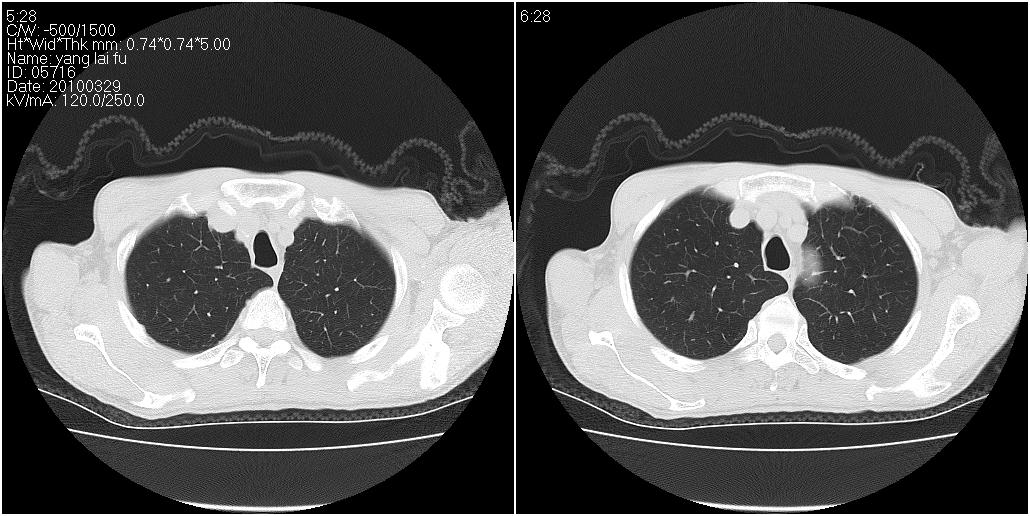

标题: CT25416:男性,70岁。胸片发现右下肺斑片状阴影 [打印本页]

标题: CT25416:男性,70岁。胸片发现右下肺斑片状阴影

考虑右肺下叶炎症可能性大?未除占位,建议增强。右下肺肺不张

右肺中叶阻塞性不张及肺炎,高度怀疑支气管占位,建议纤支镜检查!

考虑右肺中叶感染。左肺下叶支扩。

1)右肺中叶慢性炎症并支气管扩张,节段性肺不张。2)两肺下叶支气管扩张。